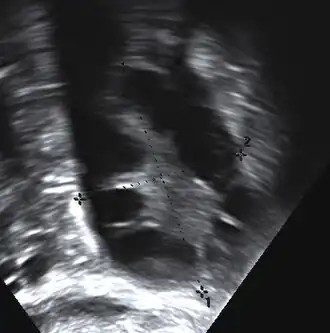

Gynecologic ultrasonography first looks for small ovarian follicles.[75] To count as polycystic ovaries, at least 20 follicles need to be present, smaller than 9 mm. This used to be 12 in older diagnostic criteria.[16] A less clear marker of PCOS is enlarged ovaries.[75] Ovary need to be at least 10 cm3 to count.[16] For sexually active individuals or those that agree, a transvaginal ultrasound approach is preferred. Alternatively, AMH levels can be tested in the blood.[75] Laparoscopic examination may reveal a thickened, smooth, pearl-white outer surface of the ovary. This would usually be an incidental finding if laparoscopy were performed for some other reason, as it would not be routine to examine the ovaries in this way to confirm a diagnosis of PCOS.[78]

-

Transvaginal ultrasound scan of polycystic ovary -

Polycystic ovary as seen on sonography